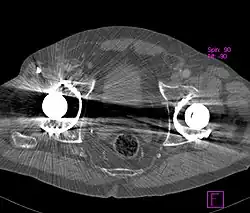

Sieht man CT-Bilder vom Menschen, ist es schwierig zu entscheiden, was echt ist und was ein durch Strahlaufhärtung erzeugter Artefakt. Eine Möglichkeit, das zu differenzieren, besteht in der Verwendung eines Phantoms. Es handelt sich um menschliche Knochen, aber die Weichteile sind durch Wasser ersetzt. Das Phantom erlaubt es, die vom Knochen verursachten Verfälschungen der CT-Werte in den benachbarten Weichteilgeweben quantitativ abzuschätzen. Sie sollten idealerweise 0 Hounsfield-Einheiten betragen. Durch den Aufhärtungseffekt entstehen in dem die Weichteile simulierenden Wasserbad teils hypodense, teils hyperdense Artefakte.